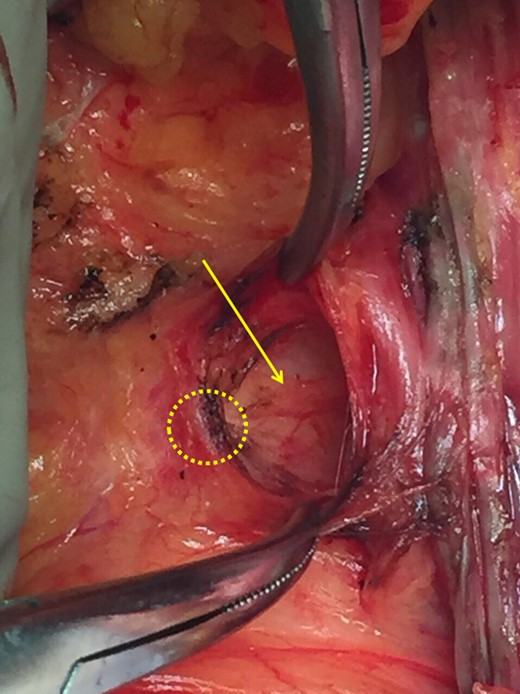

Meticulous exposure of the operating field. Yellow circle: the malignant tumor, white outline: upper external quadrant of the left breast and the left tail of Spence, thin arrow: clavipectoral fascia, thick arrow: pectoralis major.